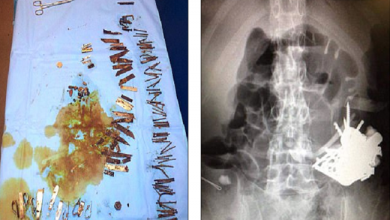

في الهند .. جراحون يخرجون 600 مسمار من معدة رجل !

إخراج مئات ” المسامير ” من بطن مريض في السعودية !